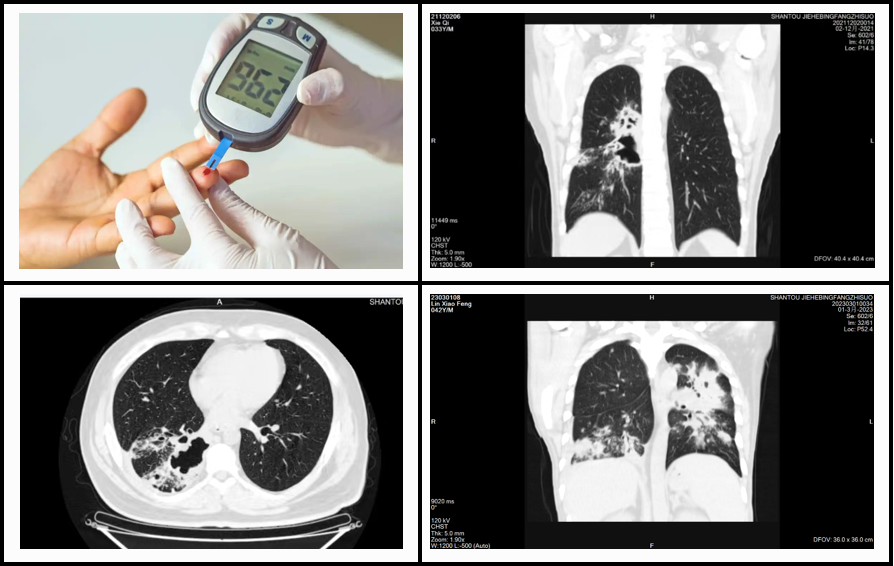

糖尿病,这个名字相信大家都不陌生。它是一种由于胰岛素分泌缺陷或作用缺陷引起的慢性疾病,长期患病会导致各种并发症。而结核病则是由结核分枝杆菌引起的一种传染病,主要通过飞沫传播,可侵犯全身多个器官。这两种疾病看似没有关联,但实际上,糖尿病人由于免疫力下降,更容易感染结核病,并且感染后的病情往往更严重。

因此,对于糖尿病人来说,进行结核病筛查是非常重要的。结核病筛查可以帮助糖尿病患者早期发现结核病,从而采取及时的治疗措施,避免疾病的进一步传播和恶化。同时,早期发现和治疗结核病可以降低糖尿病患者发生并发症的风险,提高生活质量。结核病筛查的方法包括症状筛查、胸部 X 光检查、结核菌素试验(PPD 试验)和痰液检查等。

如果糖尿病患者被确诊为结核病,应立即到结核病定点医疗机构进行规范的抗结核治疗。在抗结核治疗的同时,糖尿病患者需要更加密切地监测血糖水平,调整糖尿病治疗方案,以确保血糖控制在理想范围内。